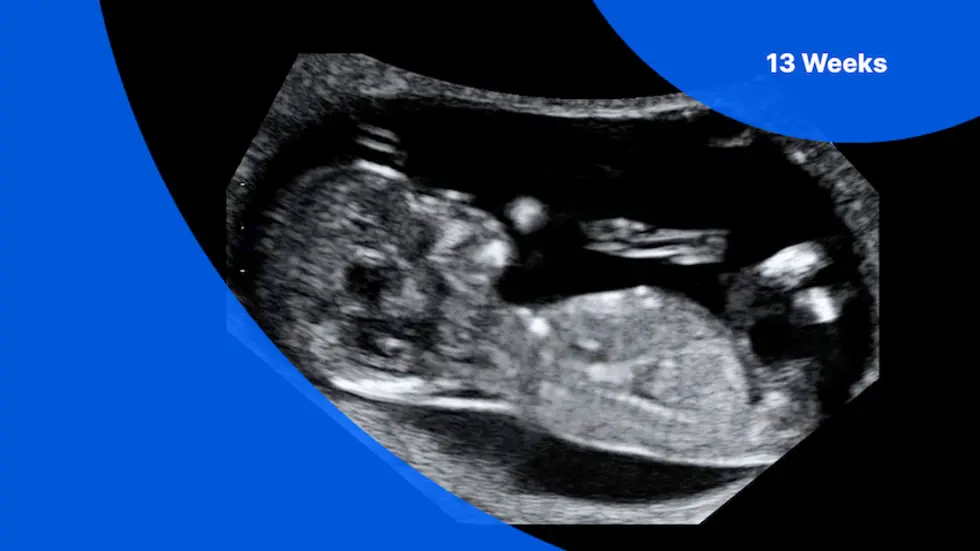

Your 13-Week Pregnancy Ultrasound: A Family-First Look at Development

The 13-week pregnancy ultrasound is more than just a picture; it’s a comprehensive medical assessment. During this non-invasive scan, our specialists meticulously examine various aspects of your baby’s health and development. You will see your baby’s overall growth, confirm the due date, and observe their active heart rate. We also check for the proper formation of vital organs and assess the amount of amniotic fluid surrounding your baby, which is crucial for their well-being.

A key component of this scan is the **nuchal translucency (NT) screening**. This specialized measurement evaluates the fluid at the back of your baby’s neck, providing an early assessment of the risk for chromosomal anomalies such as Down syndrome. While it’s a screening tool, not a diagnostic one, it offers valuable insights, allowing you and your healthcare provider to consider further testing if indicated. A normal NT range at 13 weeks typically falls below 3.5 millimeters. Understanding these results is an important step in your prenatal care.